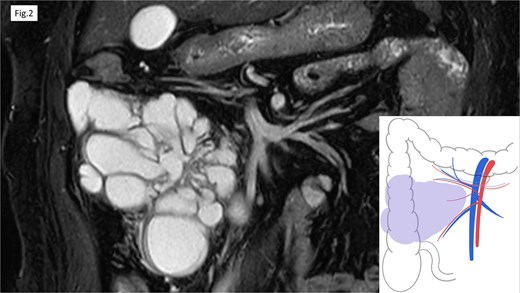

Computed tomography (CT) revealed cystic lesions located in the mesentery of the right colon, without apparent connection to the gastrointestinal tract (Fig. 1). Magnetic resonance imaging (MRI) confirmed the presence of multiple non-enhancing cystic lesions (Fig. 2). Radiological findings suggested that the cysts were confined to the mesentery of the ascending colon, delineated by the ileocolic artery and vein (ICA/V), the right margin of the superior mesenteric vein (SMV), and the right branch of the middle colic artery (MCA-rt) and accessory right colic vein (aRCV).

MRI revealed the multifocal cystic lesions, which lacked distinct enhancement.